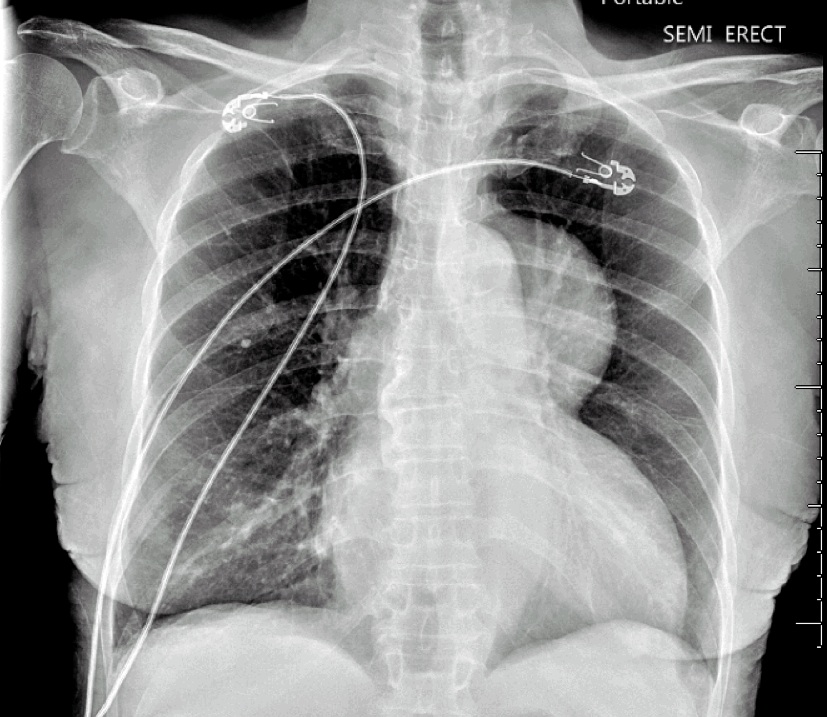

A 75-year-old African American female with congestive heart failure (ejection fraction 20%) and hypertension presented from home with a four-month history of fatigue, weight loss, and a full body desquamating rash, which began following an upper respiratory illness. On admission, her physical exam was notable for diffuse, darkened macules with a central targetoid appearance (Figure 1), oropharyngeal candidiasis, and 2+ pitting edema from her ankles to her knees bilaterally. She received a chest X-ray to complete an infectious work-up, which revealed an incidental anterior mediastinal mass (Figure 2). A follow-up Computed Tomography (CT) of her chest confirmed a 73.4mm x 87.1mm heterogeneous mass with scattered calcifications as well as enlarged bilateral axillary lymph nodes. She underwent a biopsy of her rash and mass, which demonstrated erythema multiforme and WHO Type A thymoma, respectively. During her hospitalization, she was also found to have oropharyngeal candidiasis, MSSA bacteremia and HSV-2 skin lesions. Based on the number of infections and severity of her rash, an immunocompromised state was suspected. Serum immunoglobulins were ordered, which demonstrated a low IgG (594) and a low IgM (19). Additionally, flow cytometry revealed a low CD4 count (175), confirming a combined B and T cell immunodeficiency. This combination of hypogammaglobulinemia and thymoma led to a diagnosis of GS.